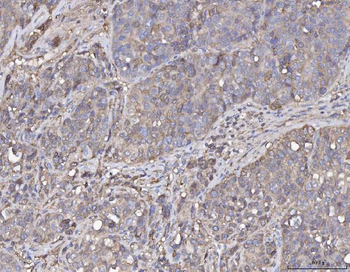

10 μg, 100 μg - Anti-S100 alpha 6/S100A6 Antibody [orb315184]

FC, ICC, IF, IHC, WB

Human, Mouse, Rat

Rabbit

Polyclonal

Unconjugated

10 μg, 100 μg - Anti-HSD11B2 Antibody [orb316541]